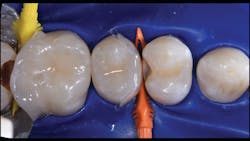

In the following case study (figures 1–11), the techniques and methods discussed will be demonstrated with the treatment of a quadrant of four posterior restorations. Four interproximal smooth-surface carious lesions are conservatively treated with two nonretentive saucer preparations and two marginal ridge-preserving opportunistic preparations.